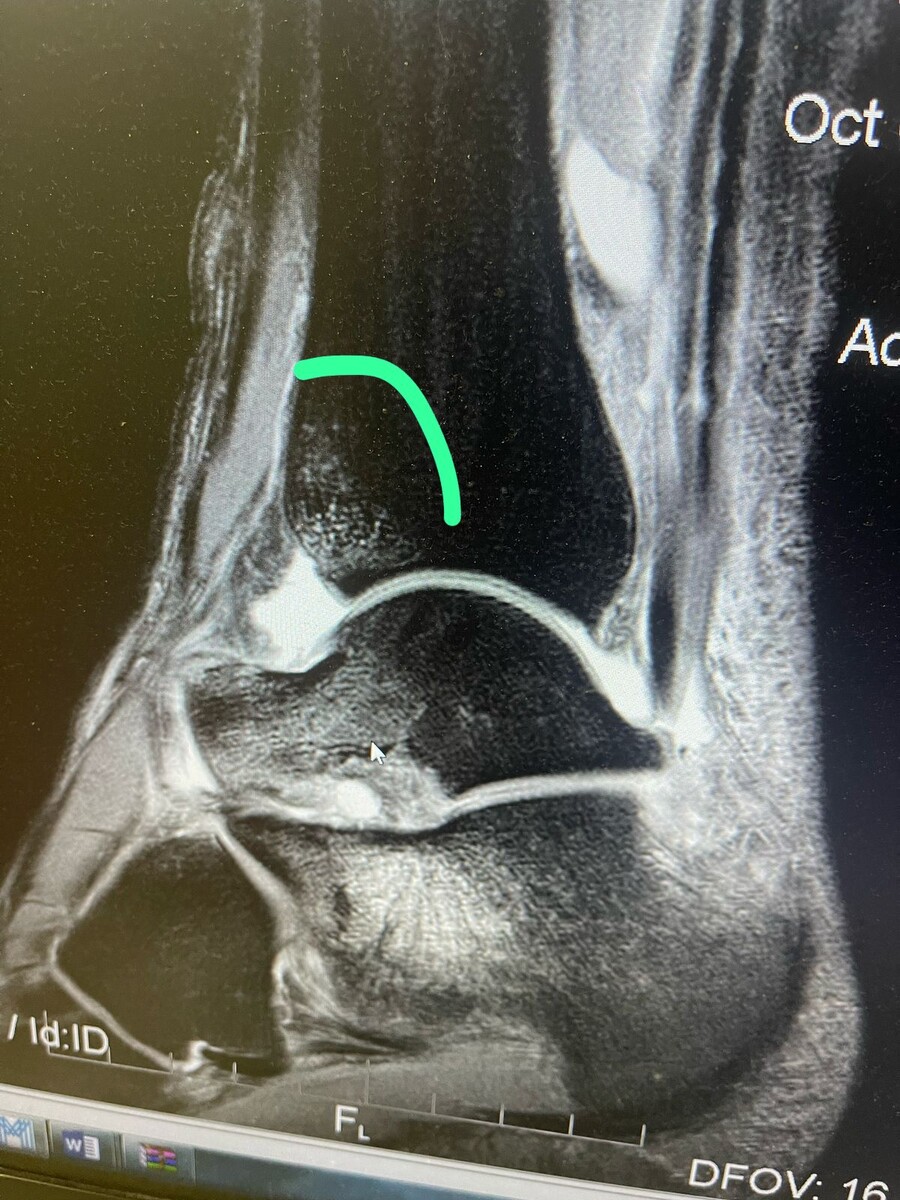

Снимок поврежденного голеностопного сустава

Такой вывод я сделал после полученной травмы на ультрамарафоне🏃 Atakama Crossing. На фото - третий день забега: я преодолеваю реку, прыгая с камня на камень. В какой-то момент я с разбега прыгнул в воду, услышал хруст и почувствовал сильную боль в области голеностопного сустава. Я перешел на шаг, но позже разбежался и продолжил гонку. После финиша заметил появление отёка. Отёк и боль не прошли и после возвращения домой.

Я обратился к своему другу — спортивному доктору Никите Зайцеву, сделали снимок, диагноз неутешительный — перелом. Впереди курс реабилитации и 2 месяца без бега😔 Обидно, конечно, но это хороший урок, которым я считаю необходимо поделиться со всеми: никогда нельзя прыгать в воду, лучше обезопасить себя и перейти на шаг.